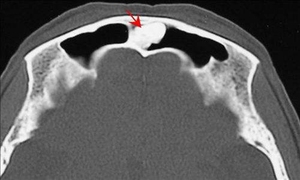

骨瘤,中医病名。是指以肿块坚硬如石,紧贴于骨,推之不移为主要表现的肿瘤性疾病。又称石瘤。骨瘤为良性骨肿瘤,好发于青少年。95%以上发生在颅骨和鼻副窦内。发生在颅骨外板者,局部有坚硬无痛之肿块隆起。发生在颅骨内板或鼻副窦者,可能有相应的压迫症状,如眩晕、头痛等,骨瘤很少恶变。本病相当于西医的骨良性肿瘤、恶性肿瘤。

好发于颅骨、颜面骨及下颌骨,一般无症状,病程经数年或数十年;若发生于颅骨内板可能引起颅内压增高和脑压迫症状,如头晕、头痛,甚至癫痫等;当肿瘤发生于颅骨外板时,可造成外貌畸形,若发生于下颌骨,口腔或鼻腔内常引起压迫症状;颅骨区外骨瘤有时可出现恶变。